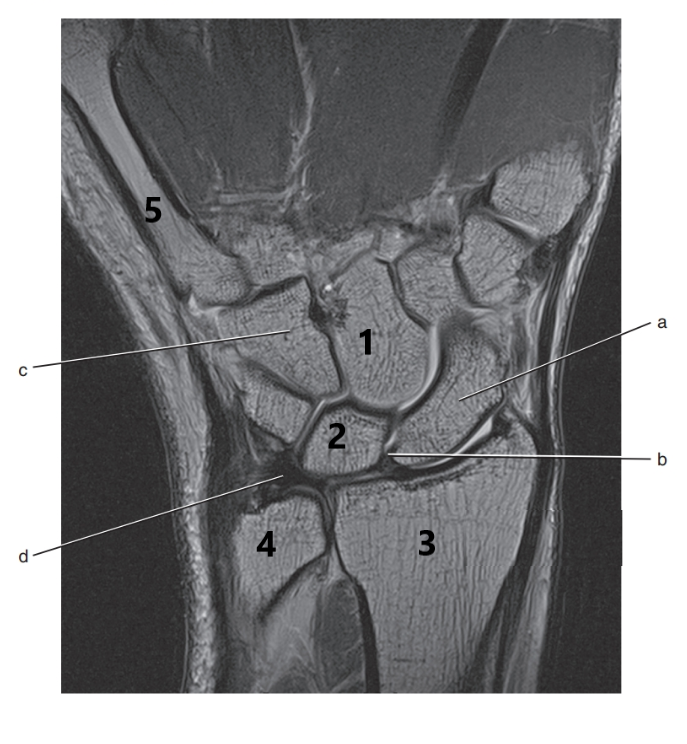

What is # 3 ?

Radius

What is # 2 ?

Lunate

Scaphoid

Triangular fibrocartilage complex